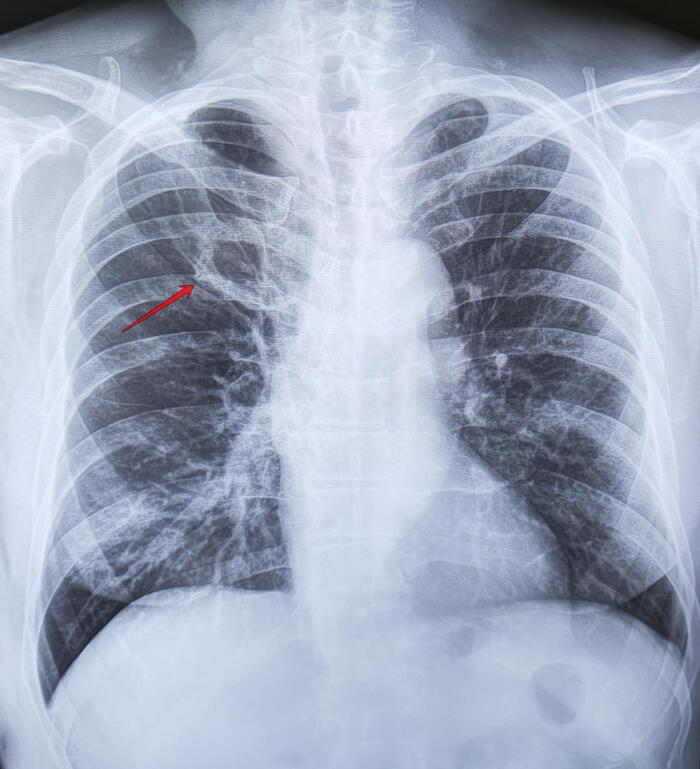

Ребро Люшка

Ребро Люшка - врожденная аномалия развития ребра в виде удвоения его переднего отдела

-Иногда ошибочно принимается за опухоль или фиброзные изменения.